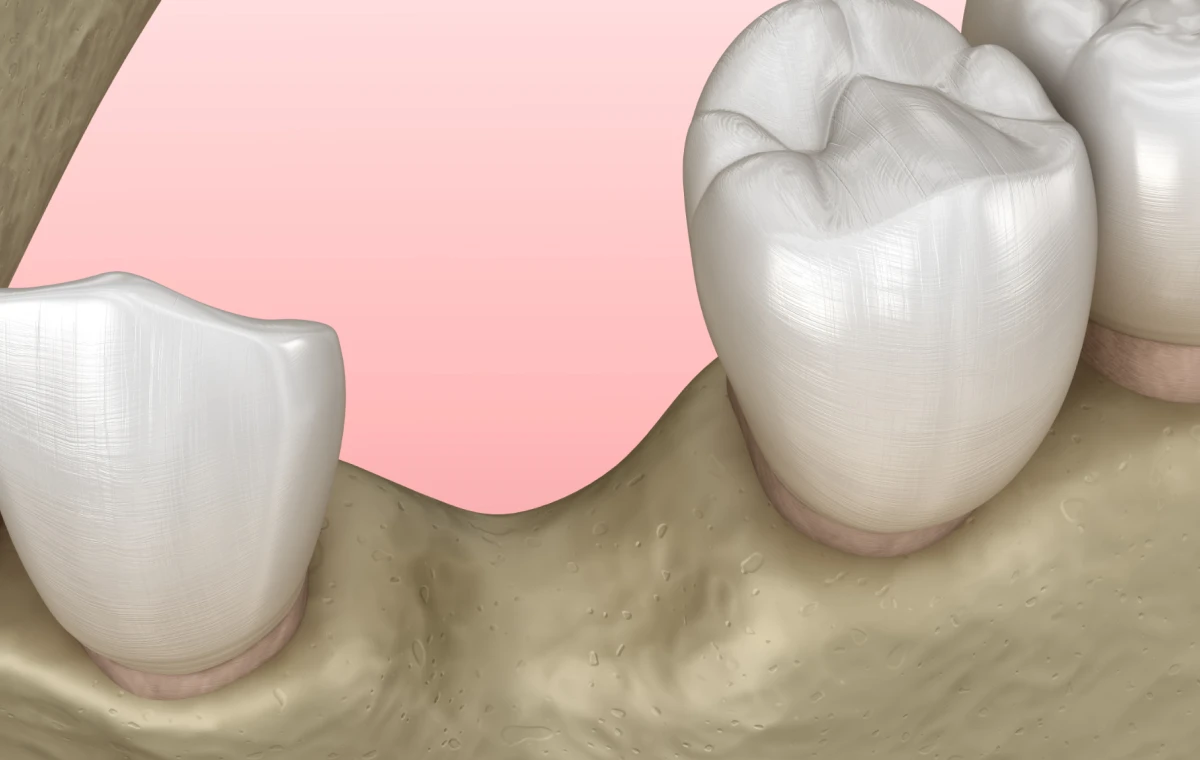

Pourquoi une perte osseuse survient-elle ?

Après une extraction dentaire

Une résorption osseuse est quasi inévitable après le retrait d’une dent. On estime que 40 % du volume osseux peut être perdu durant la première année.

La régénération osseuse guidée est indiquée pour :

- Augmenter le volume osseux avant la pose d’implants.

- Restaurer une zone atrophiée après extraction.